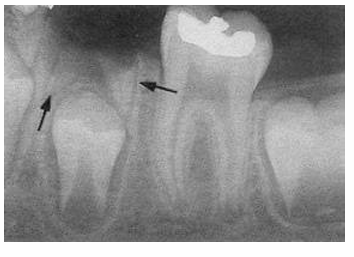

may take ____ demineralization to occur before it will be evident radiographically

-30-70%